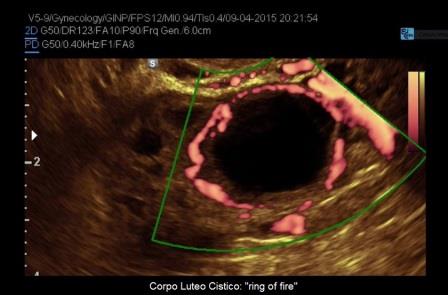

Uno degli aspetti più tipici del corpo luteo e delle cisti luteiniche è la ipervascolarizzazione periferica che si evidenzia al power-Doppler come un intenso anello di colore "ring of fire" (anello di fuoco). Ciò è legato alla intensa neoangiogenesi delle cellule tecali luteinizzate presenti nella parete del corpo luteo.

Per quanto riguarda le neoplasie abbiamo visto come il corpo luteo cistico può assumere l'aspetto di una Cisti Uniloculare Solida dove la componente solida è rappresentata dal coagulo endocistico. Un valido aiuto nella diagnosi differenziale ci è dato dal power-Doppler che ci consente di valutare le differenze di vascolarizzazione tra Cisti Luteinica e Cisti Uniloculare Solida di altra natura. La Cisti Luteinica ha una componente solida endocistica rappresentata dal coagulo che non è vascolarizzato al power-Doppler mentre presenta una parete riccamente vascolarizzata (ring of fire). Le Cisti Uniloculari Solide di altra natura possono avere una parete vascolarizzata ma non in maniera così intensa come per il corpo luteo ed hanno una componente solida (papille e parti solide) che può avere un Color Score variablie da 2 a 4.